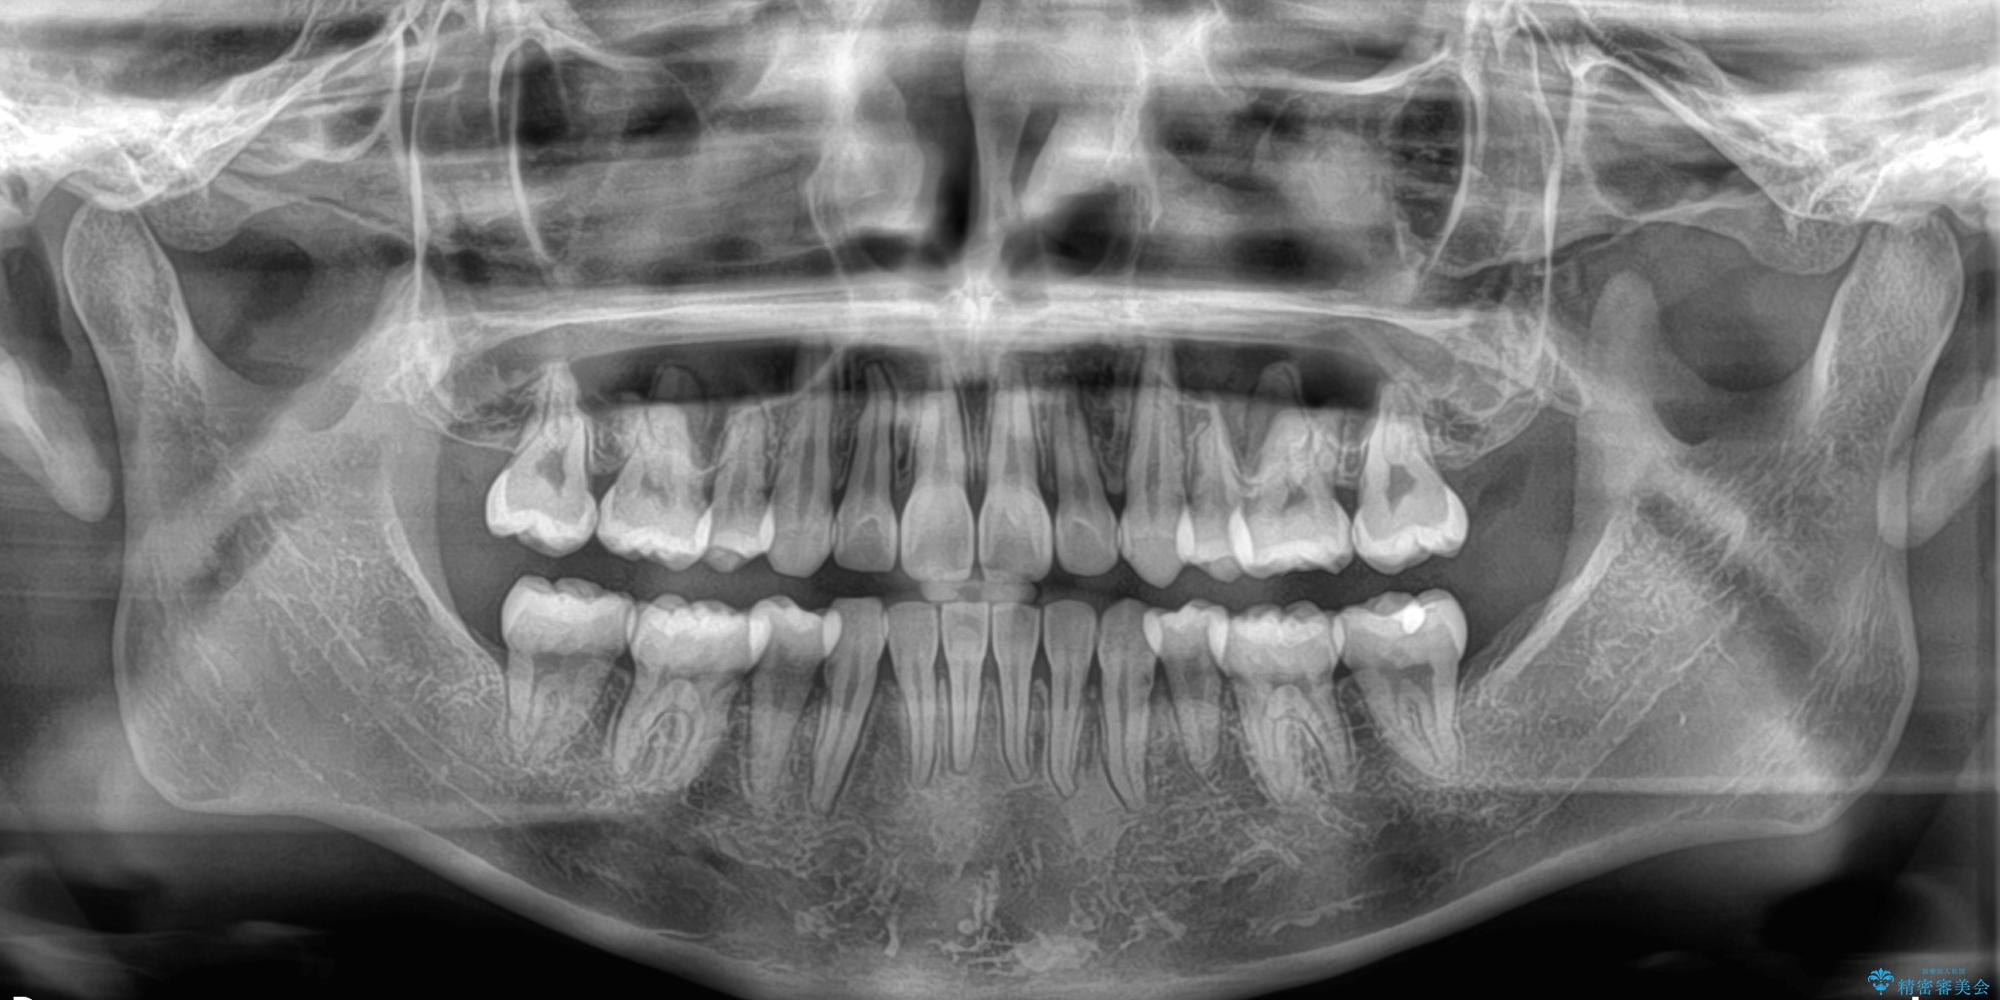

- 口を閉じたときに飛び出してしまう上顎前歯を気にして来院された患者様です。

下顎はデコボコが気になっていたため、上下左右第一小臼歯4本を抜去して、ワイヤー装置にて口元の突出感を改善するよう矯正治療を行うこととしました。